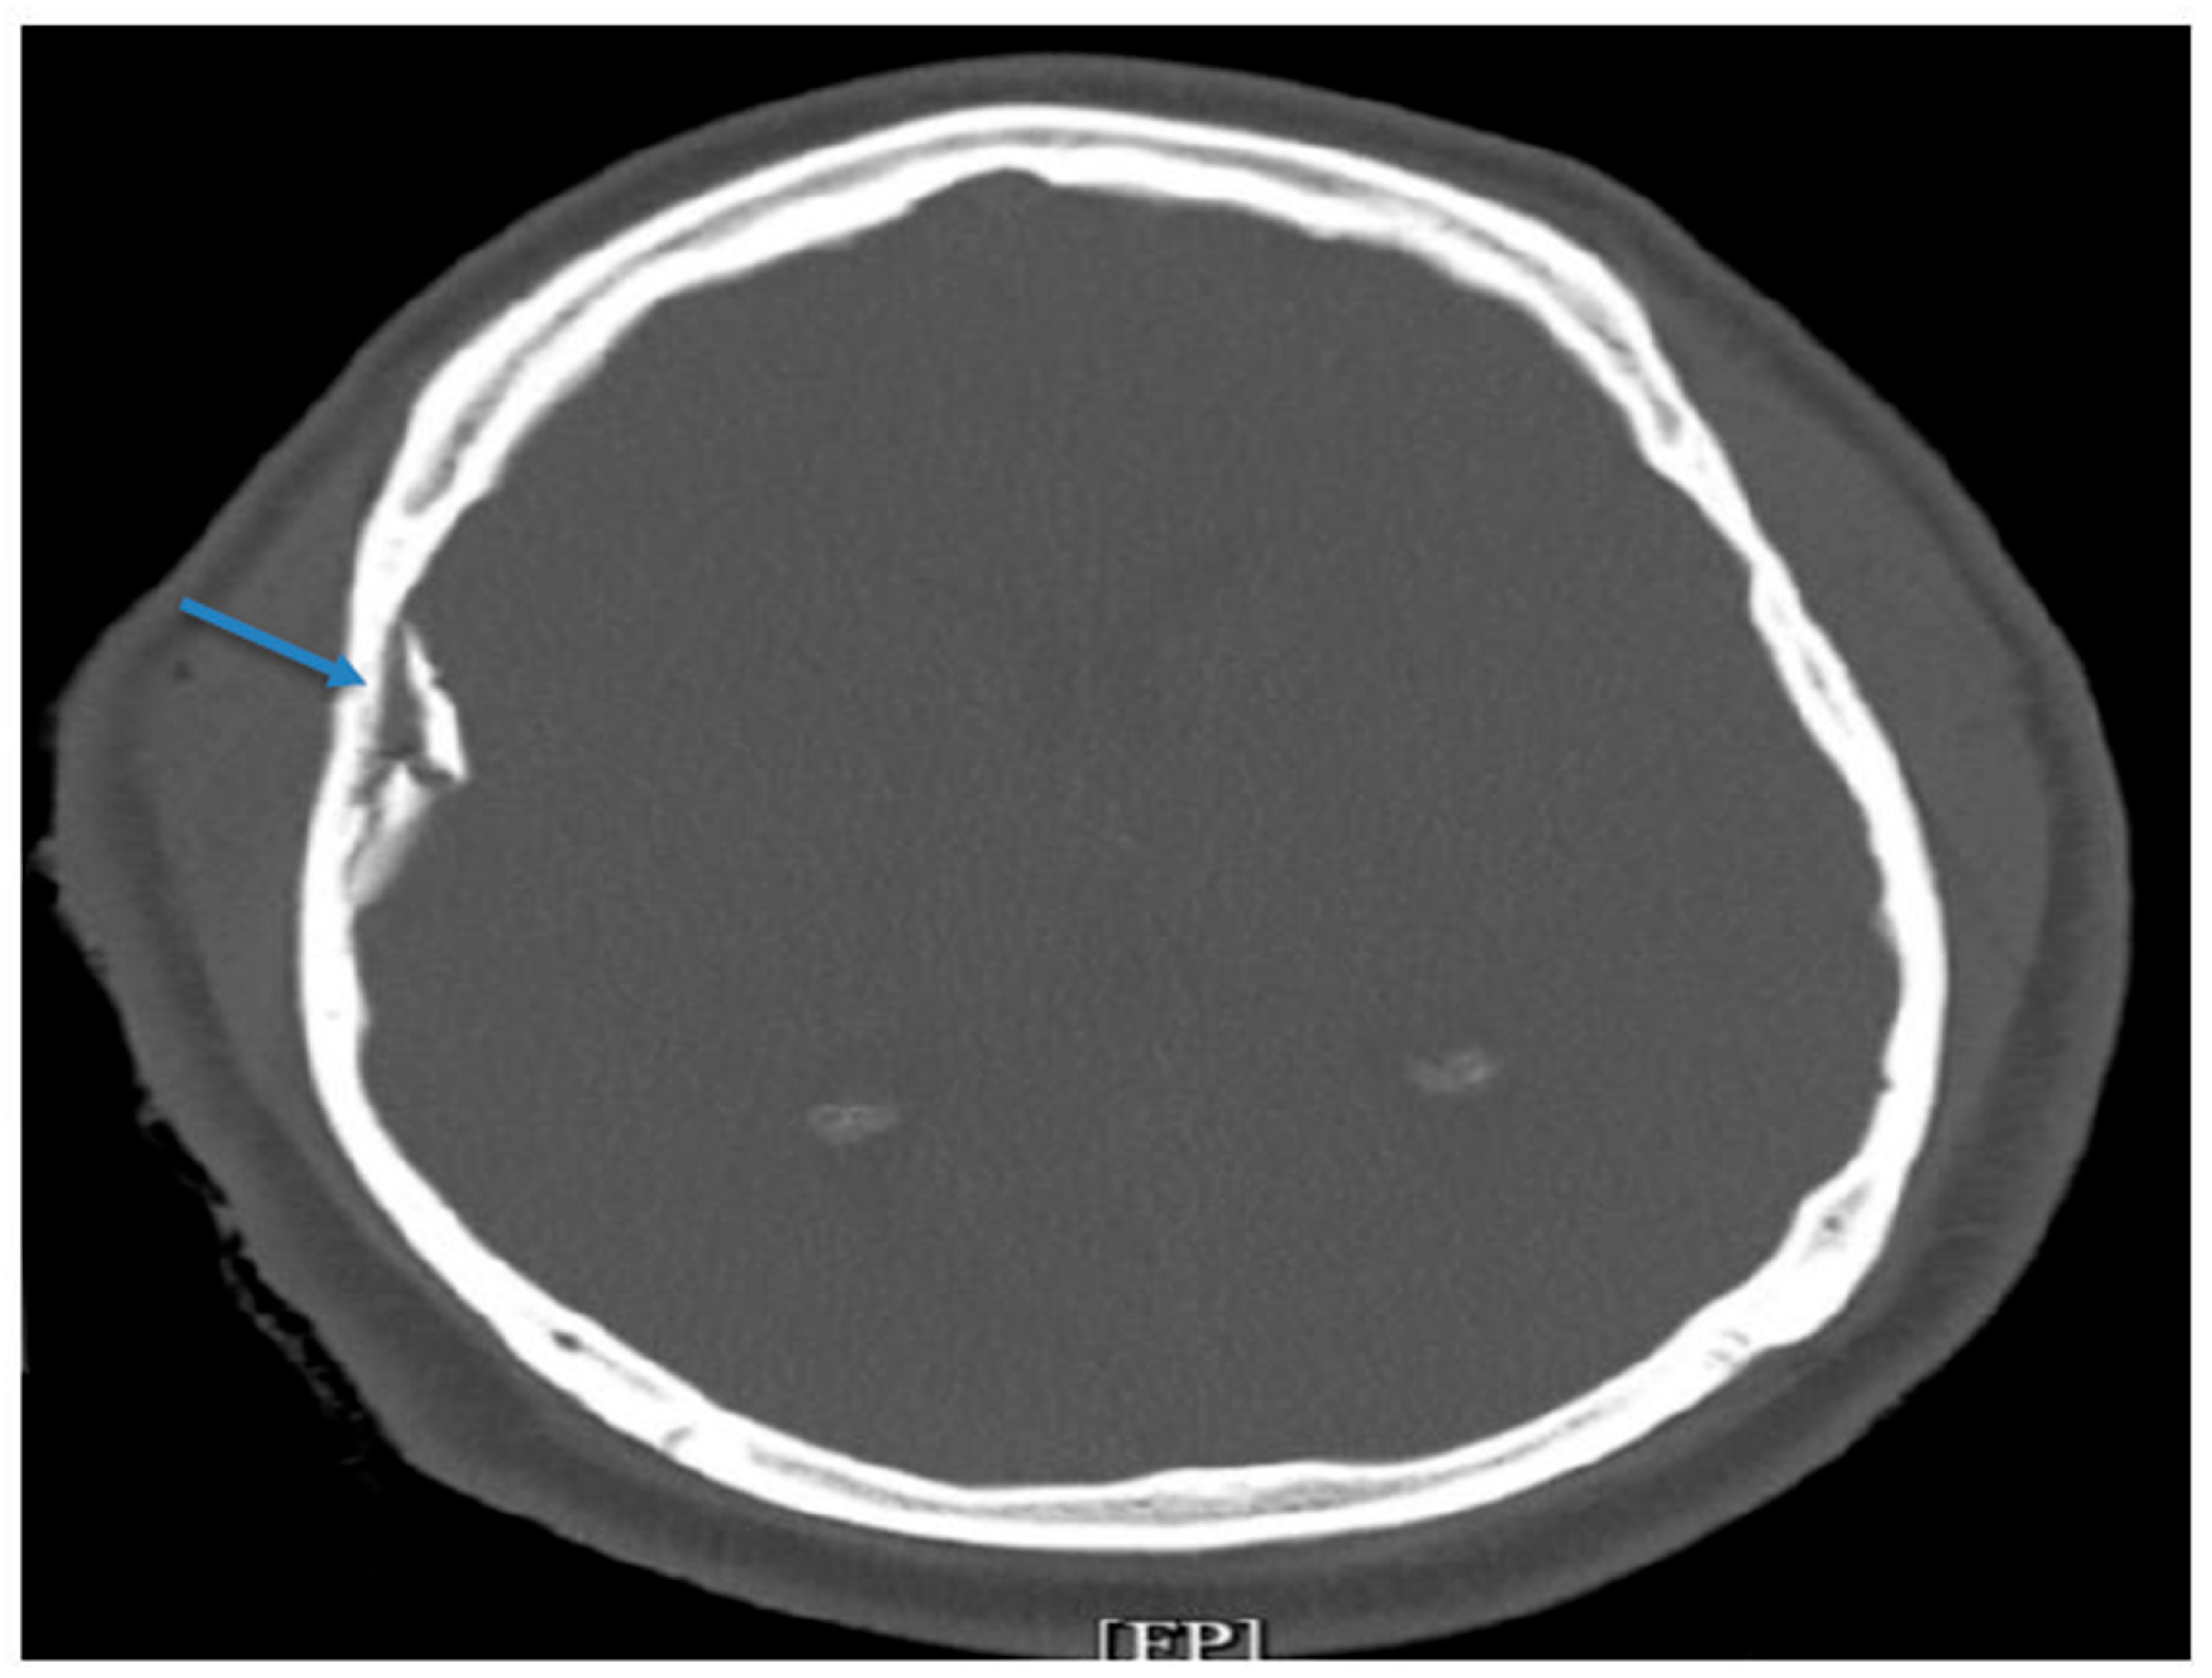

A non-contrast CT scan of the head revealed an acute, depressed, and comminuted right temporoparietal skull fracture with a small associated contusion but no midline shift (Figure 1). There was also mild pneumocephalus and scattered subarachnoid hemorrhage. Additional imaging demonstrated bilateral displaced humeral head fractures with posterior glenohumeral subluxation, consistent with impact injuries sustained during the assault. The neurosurgical team performed an urgent craniotomy with elevation of the right temporal bone fracture and removal of the associated hematoma. An External Ventricular Drain (EVD) was placed intraoperatively to monitor intracranial pressure (ICP) and allow cerebrospinal fluid diversion.

Figure 1. CT imaging acute depressed and comminuted right temporoparietal skull fracture (blue arrow).